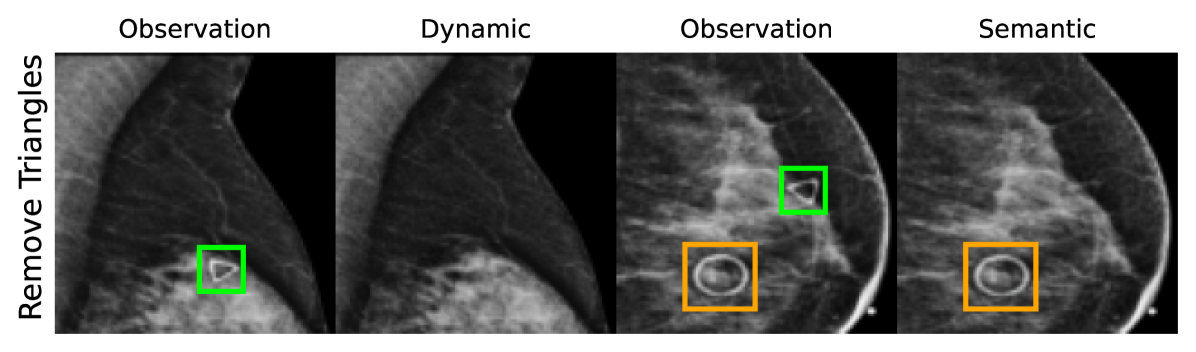

EMBED

Using prior insights, we apply our mechanisms to a real-world artefact removal task on the EMory BrEast imaging Dataset (EMBED) (Jeong et al., 2022). Schueppert et al. (2024) observe that triangular and circular skin markers are spuriously associated with breast cancer in classifiers due to shortcut learning (Geirhos et al., 2020), and manually labelled 22,012 affected mammograms. Using this dataset, we train a significantly scaled-up, amortised, anti-causally guided semantic mechanism () to remove skin markers. We model triangular markers (), circular markers (), breast density (), and cancer () as independent parents of the mammogram , and remove artefacts by intervening on and while holding and fixed. Figure 6 shows that our mechanisms effectively remove artefacts and can disentangle representations for triangles and circles. We successfully remove of triangles and of circles in our test set - a noteworthy result given the dataset’s small size and the scarcity of labelled skin markers (Appendix I).